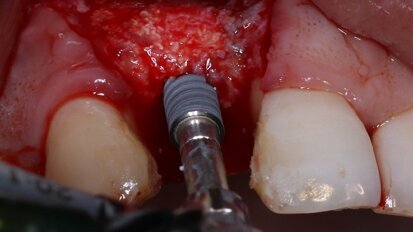

Review study compares machined and sandblasted dental implant surfaces

BUDAPEST, Hungary: Studies have shown that the implant surface roughness influences the degree of biological integration and success rates of dental ...